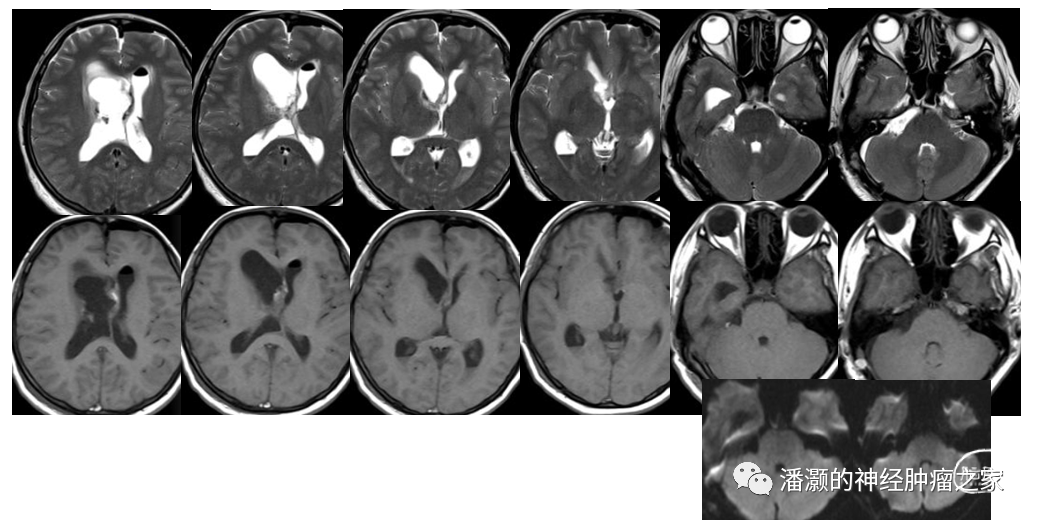

术前影像如下:

CT提示右侧CP角低密度占位,右侧脑室额角为主等低密度混杂占位,幕上脑室系统扩大。

右侧CP角占位T2高信号、T1低信号,无强化,弥散成高信号,诊断考虑胆脂瘤。

脑室内占位呈混杂信号,与丘脑、透明隔关系密切,强化明显,内有混杂信号。强化可见大脑内静脉位于肿瘤下方。结合影像特征,考虑中枢神经细胞瘤。